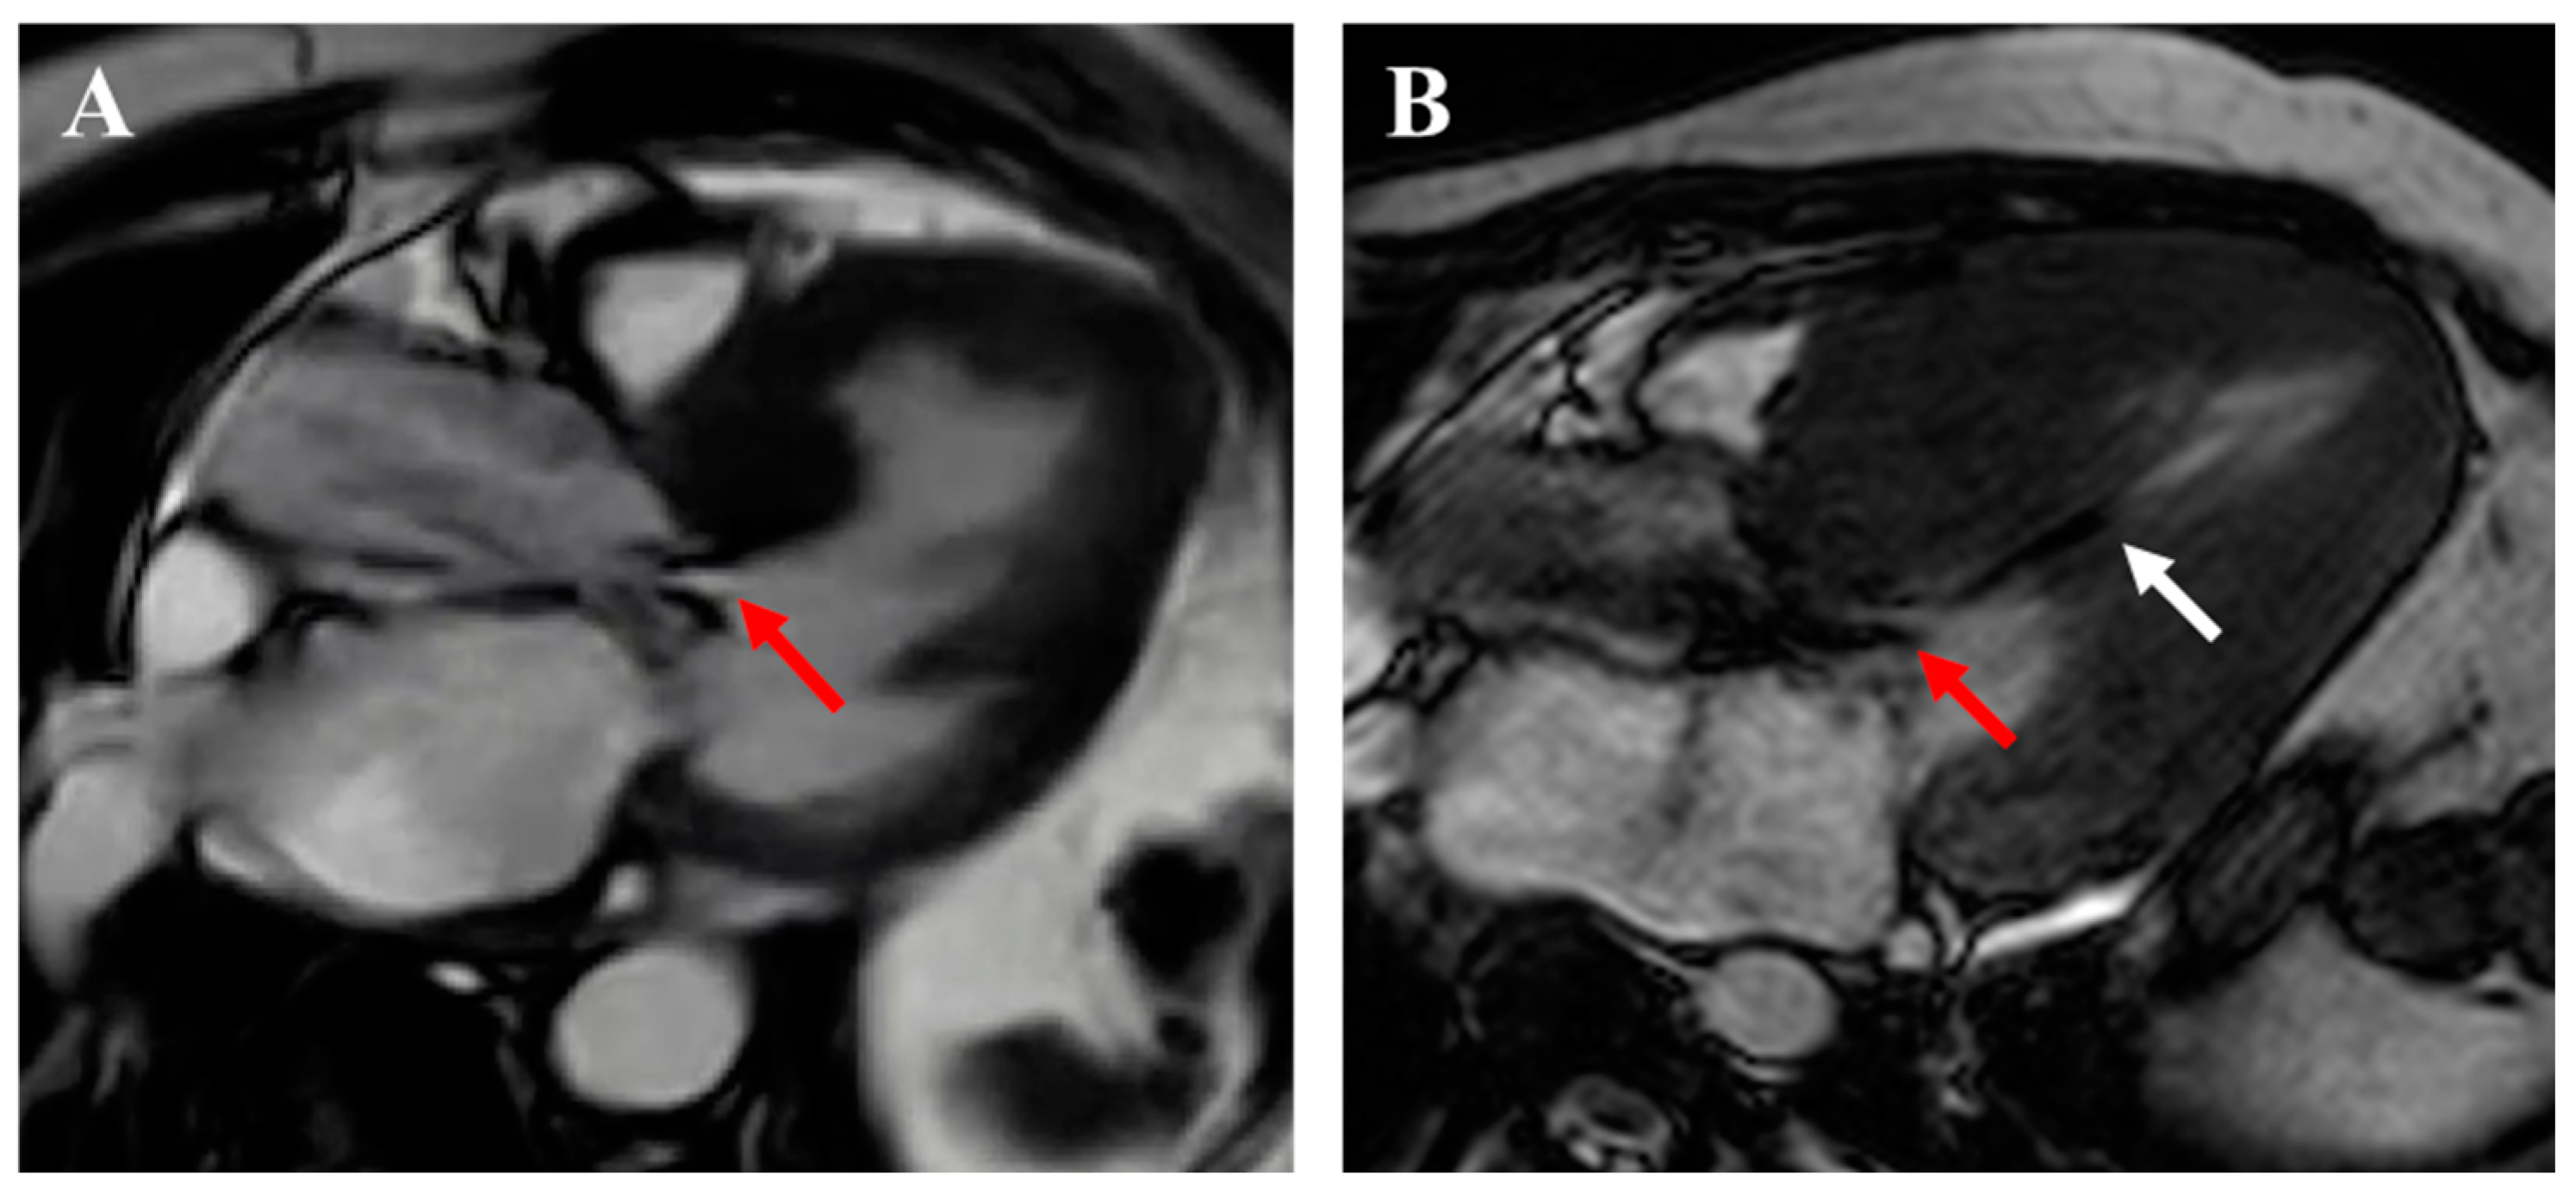

2.4. Apical Aneurysm

3.3. Cardiac Magnetic Resonance Imaging

- Rowin, E.J.; Maron, B.J.; Maron, M.S. Reply: Hypertrophic Cardiomyopathy with Left Ventricular Apical Aneurysm. J. Am. Coll. Cardiol. 2017, 70, 407. [Google Scholar] [CrossRef]